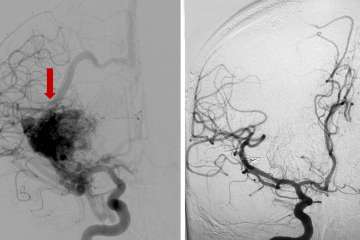

With an arteriovenous malformation, treatment decisions are nuanced and depend on whether the vessel has caused bleeding in the brain or not, says neurosurgeon Jeremiah Johnson, MD. “These complex tangles of blood vessels in the brain can rupture and cause hemorrhagic stroke,” explains Dr. Johnson. “The definitive treatment is surgery to remove the malformation, but sometimes that’s not possible due to location in the brain or other factors. For very deep or critical parts of the brain, for example, we often avoid surgery but may be able to treat with other modalities.”

If the blood vessel malformation hasn’t ruptured, ongoing monitoring can sometimes be the safest option, but each patient and each malformation is different. The preferred option to treat some AVMs may be stereotactic radiation, where radiation beams are tightly focused on the malformation but minimally impacting the surrounding normal tissues. Or it could involve embolization, or blocking off surrounding branches of the blood vessel to safely remove the malformation. UCLA provides individualized expert care for even the most complex cerebrovascular disorders. Both Dr. Johnson and Dr. Colby are dual-trained in endovascular and cerebrovascular open surgery techniques, with expertise to perform these multifaceted procedures.

“We’ve learned a great deal through studies showing that having the full arsenal of surgical techniques is important, given that these patients present differently, and that certain presentations or anatomies respond better to certain treatments,” says Dr. Colby.

Offering the full array of treatment options along with advanced imaging capabilities to guide the decision-making process, the UCLA Stroke Center is well positioned to take on these cases and to provide a customized solution for each patient. “We have multidisciplinary conferences that include specialists in neurosurgery, neurointerventional radiology and cerebrovascular neurology in which we make sure our patients receive optimal management,” Dr. Colby says. “The only way you can do that is if you offer everything and don’t have any biases about one procedure or another.”